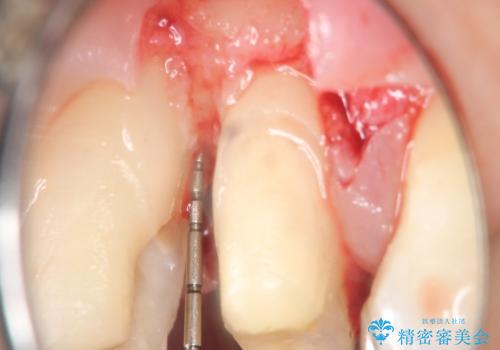

縁下カリエス オールセラミッククラウン

- 以前他院で修復した金属の詰め物の下が虫歯になっており、歯周外科を含めた歯冠修復を行っております。

歯肉縁下の虫歯は精度高い治療を行う場合、歯周外科を提案させていただくことがあります。